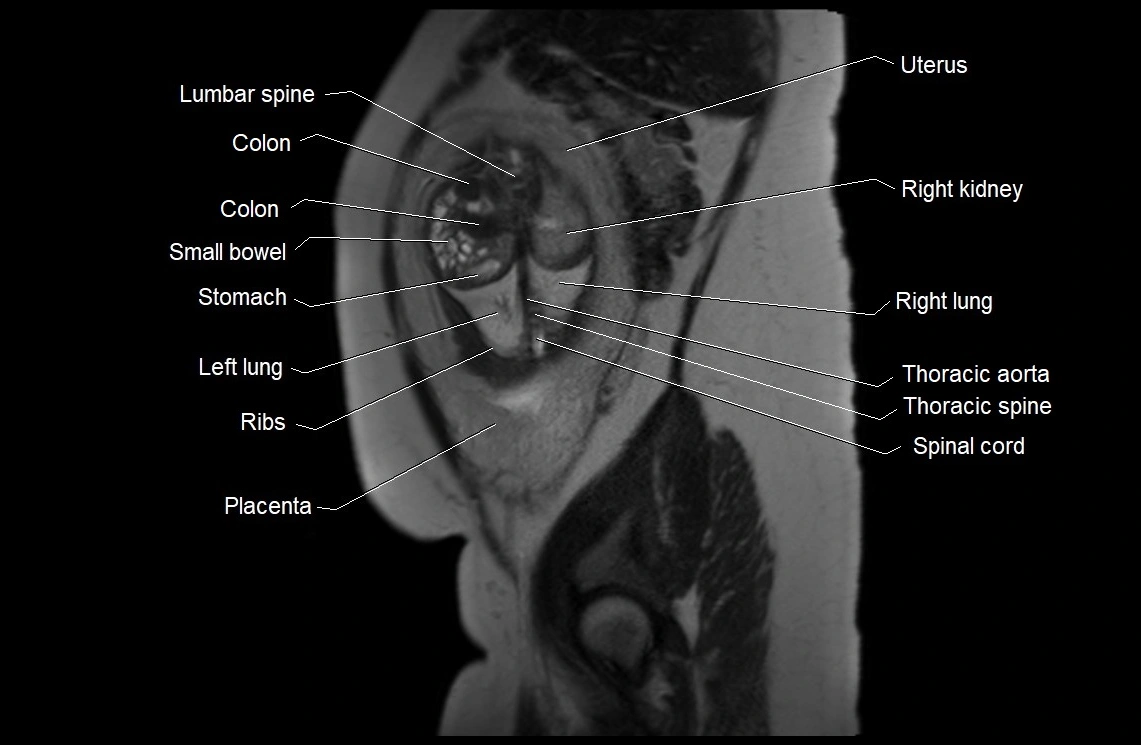

• Imaging relevance: MRI used for fetal visualization and assessing oligohydramnios/polyhydramnios when ultrasound is inconclusive

MRI Appearance

T2 HASTE (T2 GRE):

• Amniotic fluid shows very bright hyperintense signal

• Provides natural contrast against fetus and placenta

• Small particles (vernix) may appear as scattered hypointense foci within bright fluid

MRI image

image